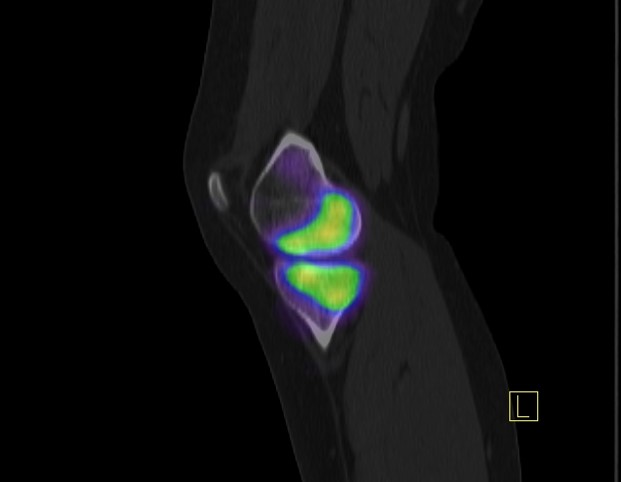

Avascular necrosis of the knee: 99mTc-HDP bone SPECT/CT and MRI Siemens Symbia Intevo, Injected dose: 680 MBq SPECT: 360°, 32 frames, 25 s/frame, 3D iterative SPECT CT: 130 kVp, 10 eff mAs, 2mm slice thickness, DLP 280 mGy*cm, multiplanar reconstructions...